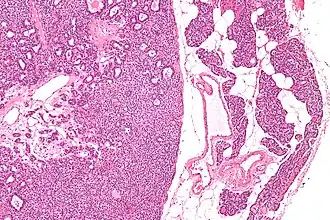

![]() Микропрепарат: аденома паращитовидной железы слева, справа — неизменённая ткань паращитовидной железы. | |

Микропрепарат аденомы паращитовидной железы. -